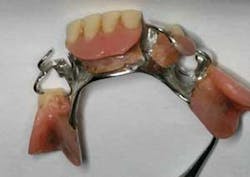

He has a partial denture to replace missing teeth on the mandible and tells you that the appliance was fabricated at least 15 years ago. Since the initial partial was made many years ago, he has lost some teeth (Nos. 28 and 29), which leads you to his main problem and why he is in your office today. His wife tells you that they were driving on the interstate last night and his partial became dislodged and “stuck in his tongue,” bleeding profusely. It became necessary for them to pull off the highway and he was able to dislodge the partial from his tongue (Figure 1).

Pathogenesis: Normally, the clinical sign of a factitial injury is one in which the patient has produced an ulceration, hard tissue damage, or trauma to any tissue. In this case, the appliance is to blame. Mr. Saunders was aware of the missing teeth and the unstable position of the appliance, but he continued to wear the appliance. He was not aware that the appliance could become imbedded in tissue, but as time has progressed, the end of the metal appliance clasp has continued to become worn and even somewhat pointed (Figures 2 and 3).